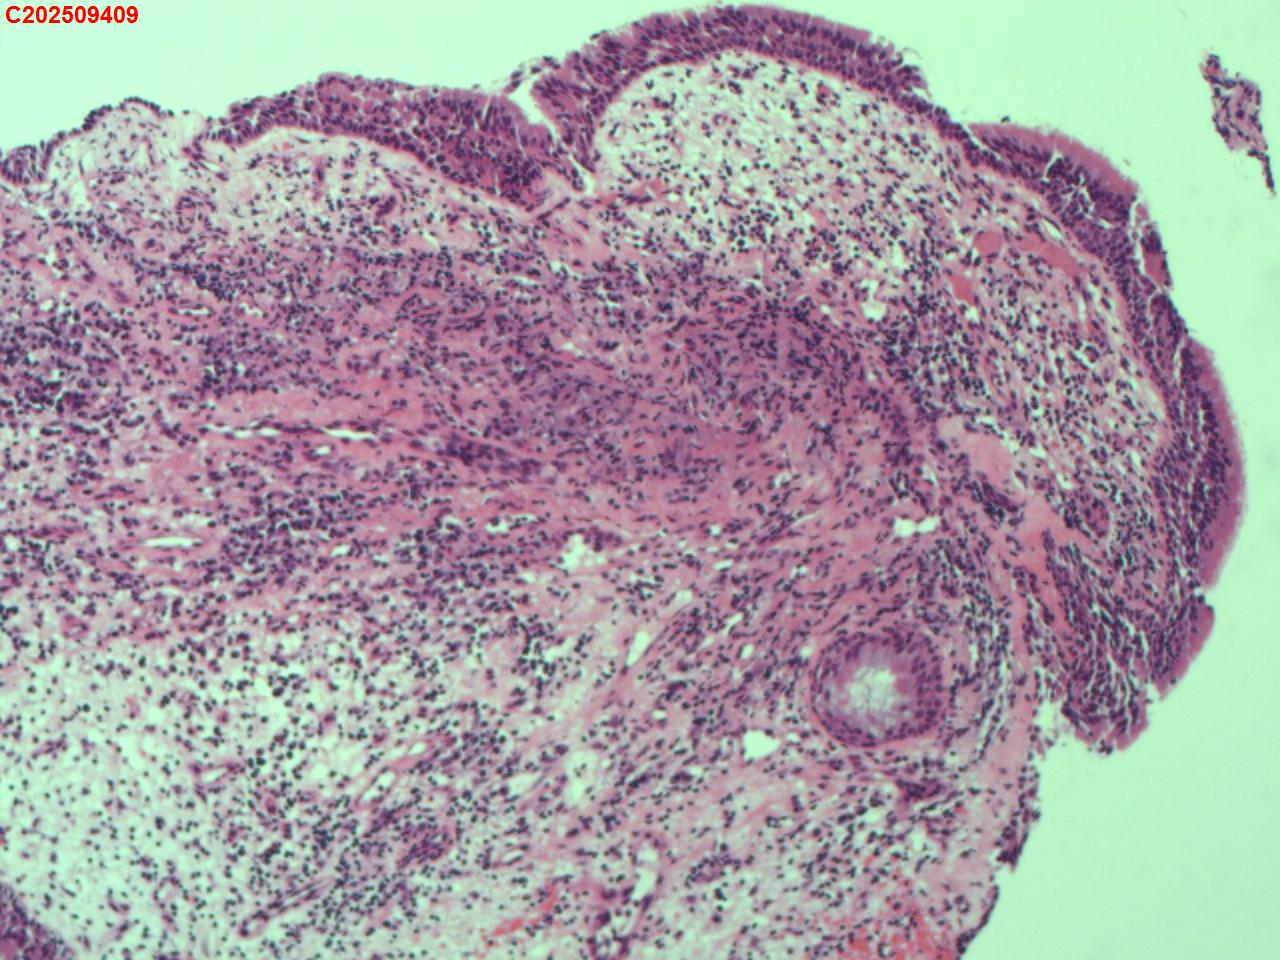

性别年龄62岁临床诊断社区获得性肺炎,肺占位性病变带除外

一般病史胸部CT:双肺可见多发斑片状、结节状高密度影,右肺上叶及左肺下叶病灶内见多发空洞,右侧少量胸腔积液。

标本名称纤支镜咬检

大体所见纤支镜:气管通畅,隆突锐利。右肺主支气管通畅,右肺上叶见少量痰液,负压吸引后见上叶开口干酪坏死物质附着,上叶各段级支气管通畅未见新生物及坏死物质,中叶、下叶背段支气管通畅,下叶基底段见新生物阻塞气道,粘膜无充血。左肺主支气管、上叶、下叶及各段级支气管通畅,粘膜无充血,未见新生物及坏死物。

考虑:支气管炎性息肉